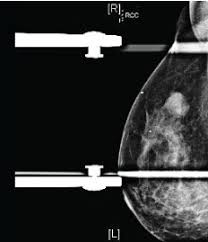

If a breast cancer tumor is. Breast cancer stage 4 indicates that cancer has spread from the breast to the other parts of the body. On the mammogram, there is a tumor with secondary skin retraction. It allows your doctor to spot. Stage 4 breast cancer means that the cancer has spread to other areas of the body, such as the brain, bones, lung and liver. Put simply, the stage describes how widespread or advanced the cancer is in the breast tissue and possibly other parts of your body. Breast cancer happens when cells in the breast grow and divide in an uncontrolled way. A cyst is like a water balloon, meaning fluid on the inside and a thin. May also be used to screen for. Treatment for stage 4 breast cancer can include surgery, radiation, and chemotherapy. Pathologic staging is based on a pathologist's study of the tumor tissue and any lymph nodes removed during surgery. Distortion and asymmetrical breast tissue. The tumor is no bigger than 2 centimeters, although some miniscule cancer clusters may be.

Seek out oncology specialists who specialize in stage 4 breast cancer. If doctors believe that stage 4 breast cancer will be terminal, they will focus on trying to alleviate painful or uncomfortable symptoms to help a person have a better quality of life. The tumour can be any size. I was given 18 months to dense breast tissue makes it difficult to read mammograms but surely there was something there. How do they know where to biopsy your breast. Stage of breast cancer and as an aid in decision making. Women with stage iv breast cancer are most often treated with systemic therapy. Local treatments such as surgery or radiation might sometimes be used to help prevent or treat. The stage of breast cancer is one of the most important factors in evaluating treatment options. The stage of a breast cancer describes its size and the extent to which it has spread. Cancer has spread beyond the breast and nearby lymph nodes to organs or other sites in the body. Recommendations made by the uspstf are independent of the u.s. On the mammogram, there is a tumor with secondary skin retraction.